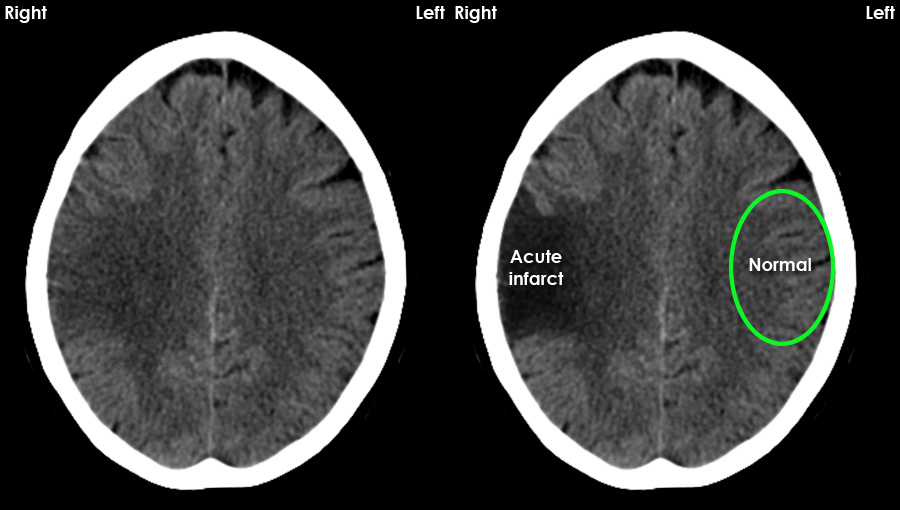

- Ischaemia: Hypodense regions in a vascular territory, loss of grey–white differentiation, sulcal effacement and early swelling.

| Acute ischaemic stroke | Area of low attenuation in a vascular territory, loss of grey–white differentiation, sulcal effacement; may have mild mass effect. |